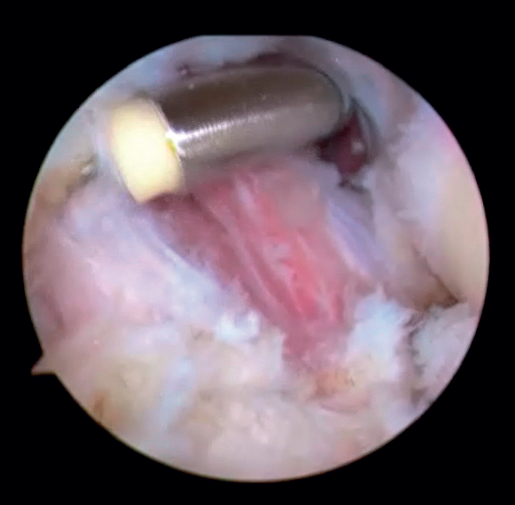

Una vez realizado el tratamiento en el compartimento posterior, realizaremos el portal proximal medial (o anteromedial), unos 2 cm proximales al epicóndilo medial y anterior al septo intermuscular medial, por donde introduciremos el trocar en dirección a la cabeza radial por delante del húmero. Una vez identificadas las estructuras articulares, realizamos bajo visión directa el portal anterolateral con técnica de fuera a dentro aproximadamente 1 cm proximal y 1 cm anterior al epicóndilo lateral(24). En este momento, se debe realizar la exéresis de los cuerpos libres, la sinovectomía, la eliminación de las adherencias tisulares y la exéresis de los osteofitos en caso de que fuera necesario. Una vez hecho esto, quedaría realizar la capsulotomía. Se puede hacer de medial a lateral o viceversa, con vaporizador o pinza de tipo basket. La preferencia de los autores es realizarla 1 cm proximal a la punta de la coronoides y anterior a la cúpula radial, de lateral a medial y usando un vaporizador de tipo hook o “gancho” (Saber 30®, Smith & Nephew) (Figura 5) que añade precisión en la profundidad del corte para evitar lesionar estructuras neurovasculares próximas a la cápsula articular. Una vez completada la capsulotomía anterior, se aprecia el tejido muscular del músculo braquial (Figura 6).